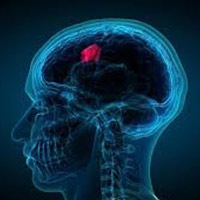

(8) Brain tumours are very rare, but some tumours are possible to detect during an eye examination. A brain tumour can trigger a rise in intracranial pressure which causes the optic disc to swell. This can sometimes be seen when looking into the eye. It often occurs in the earliest stages before symptoms such as headaches or nausea.